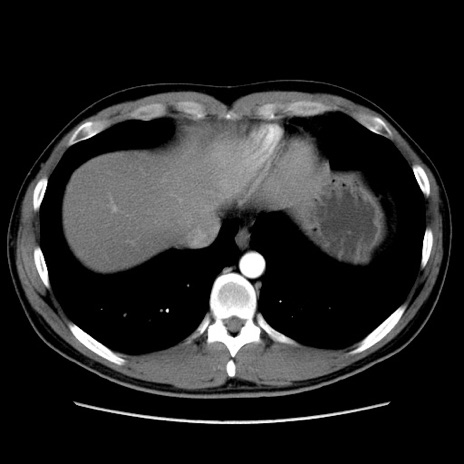

症例36(横断像)

【症例】20歳代 男性

【主訴】心窩部痛

【現病歴】今朝より上腹部痛あり。一旦軽快していたが再度出現したため救急要請。昨日夕に白身の魚を含む刺身を食べた。

【身体所見】BP 136/89mmHg、HR 74/min、BT 37.0℃、腹部:膨満、軟、心窩部に圧痛あり。反跳痛なし、筋性防御なし、腸雑音やや亢進あり。

【データ】WBC 17700、CRP 0.48